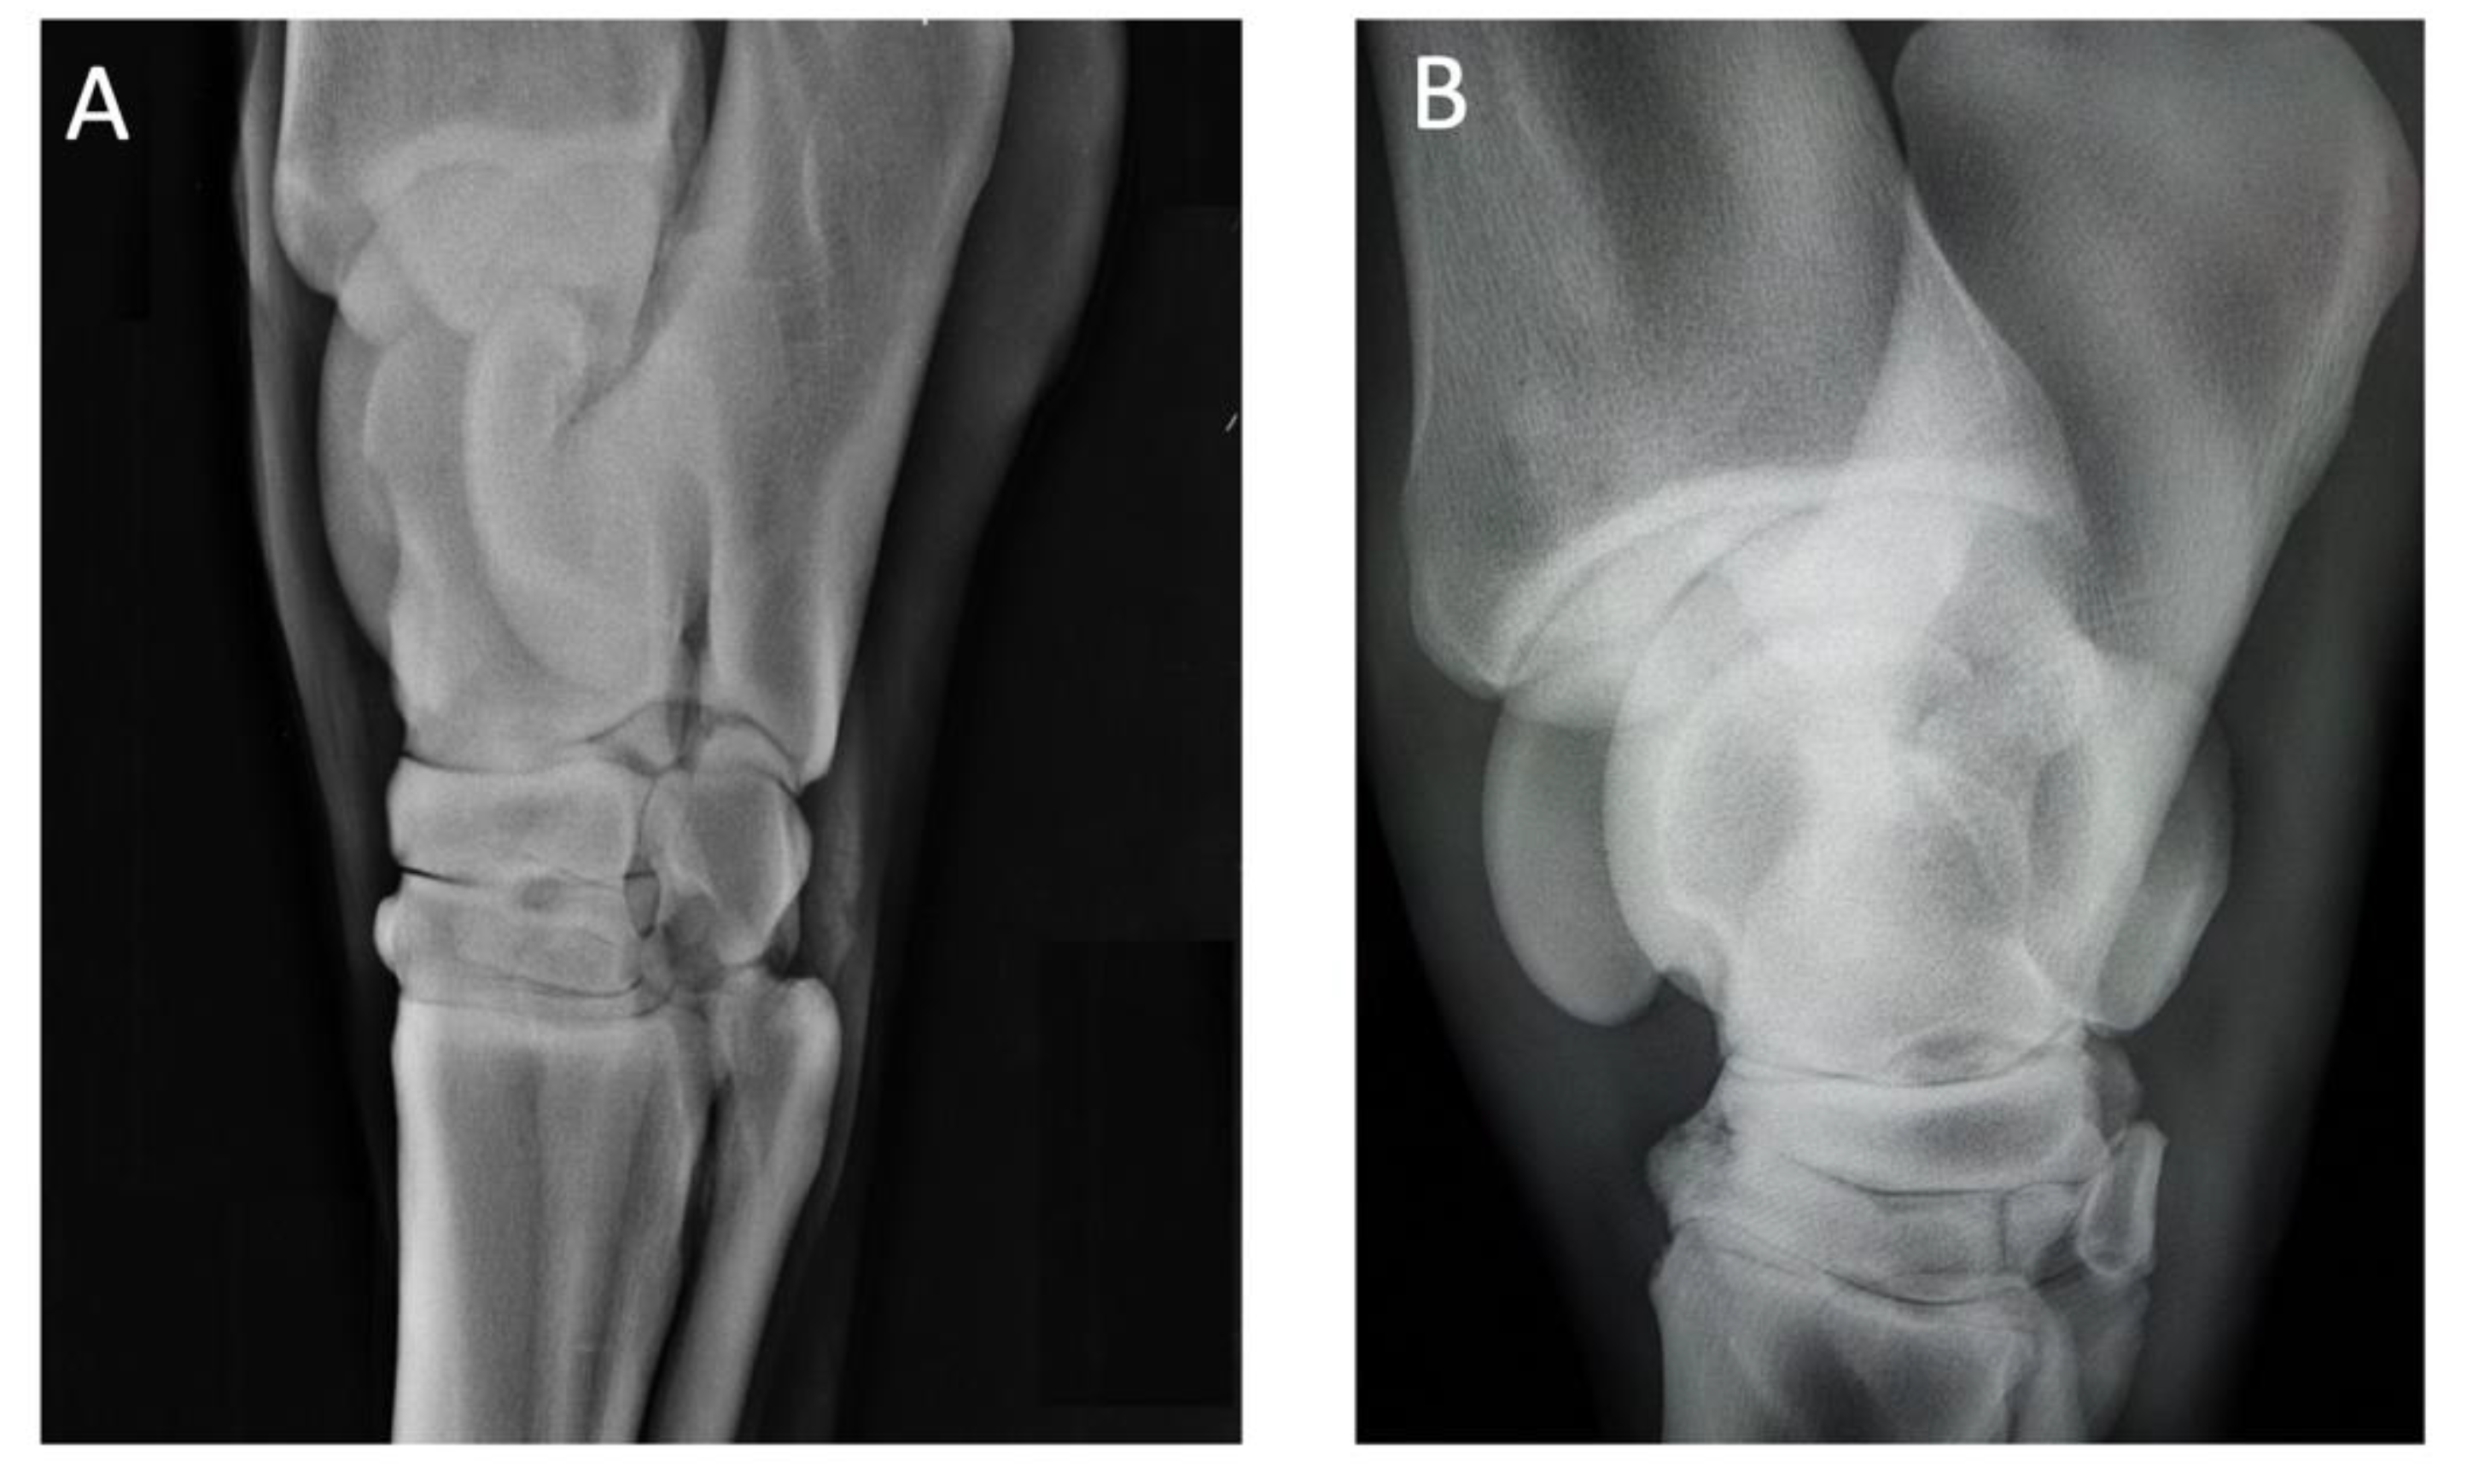

| (2) 16-year-old NRPS gelding jumping horse | Navicular syndrome and distal interphalangeal joint arthrosis of the right anterior limb | Lameness Flexion test | 3 3 | 2 3 | 2 2 | 1 1 | 0 0 |